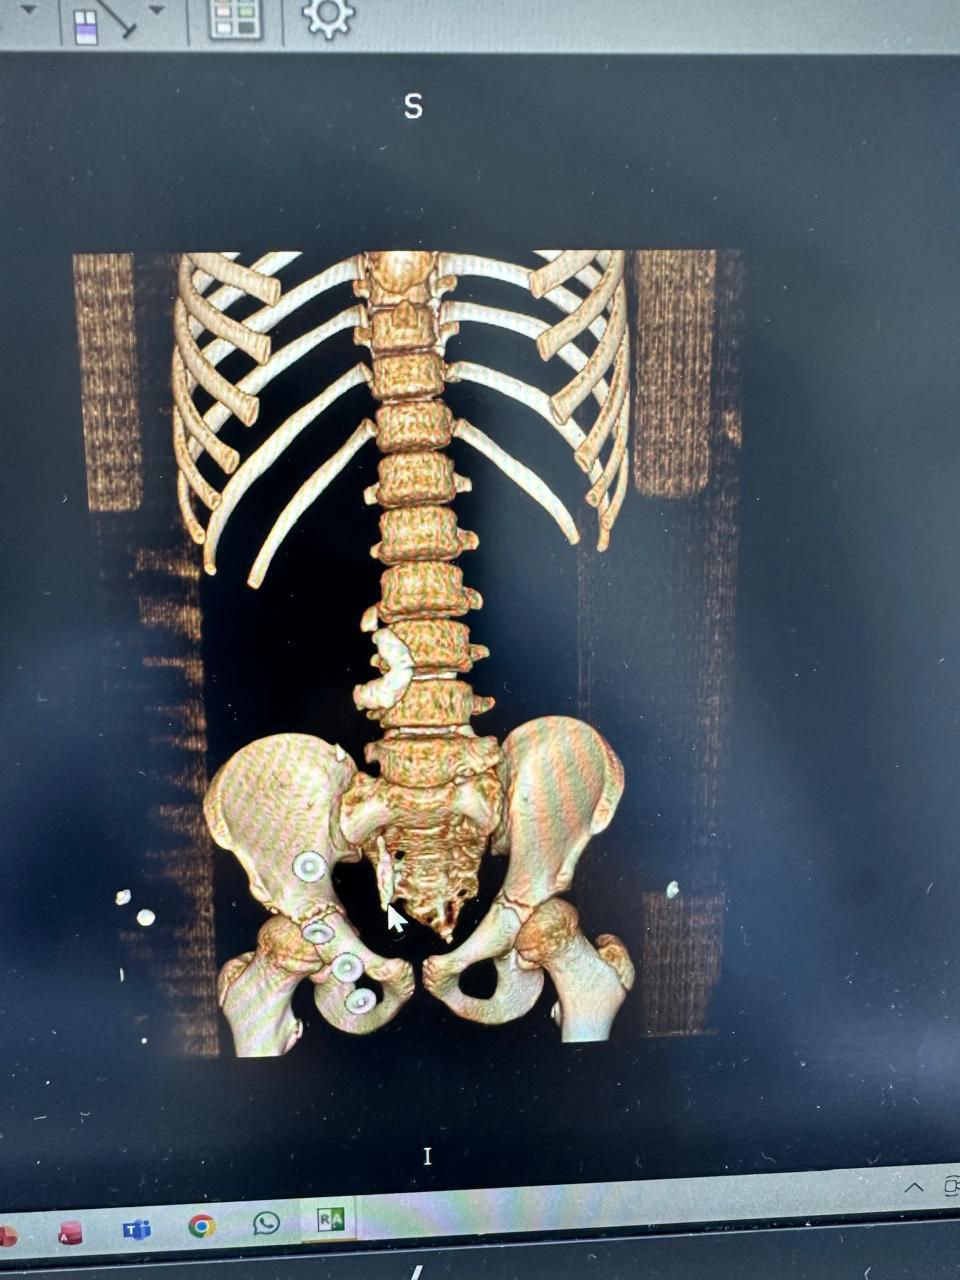

تمكن طبيب عراقي يعمل في مستشفى سفير الامام الحسين (عليه السلام) الجراحي من انقاذ مريض من عملية رفع احدى كليتيه أو إجراء أي تدخل جراحي مفتوح رغم انه كان يعاني من كلية هاجرة مترافقة مع حصاة قرن الغزال، إضافة إلى حصاة حالب كبيرة بطول (25 ملم)، وهي من الحالات المعقّدة التي تتطلب دقة عالية في التشخيص والتدخل العلاجي.

وقال المدير الاداري للمستشفى المهندس "عباس عبد علي" في تصريح خص به وكالة نون الخبرية ان" مستشفى السفير الإمام سجّل إنجازا طبيا متقدما يضاف إلى رصيده في العمليات التخصصية الدقيقة، بعد نجاح احد اطبائه الجراحين وهو الدكتور "منتظر جمال" المتخصص في جراحة الكلى والمسالك البولية، في إجراء عملية نوعية لمريض يبلغ من العمر (14 عامًا)، كان يعاني من كلية هاجرة مترافقة مع حصاة قرن الغزال، إضافة إلى حصاة حالب كبيرة بطول (25 ملم)، وهي من الحالات المعقّدة التي تتطلب دقة عالية في التشخيص والتداخل الجراحي، وتمكّن الطبيب الجراح والفريق الطبي المساعد من تفتيت الحصى بالكامل باستخدام تقنية الناظور والليزر، دون اللجوء إلى رفع الكلية أو إجراء أي تدخل جراحي مفتوح، وهو ما أسهم في تقليل المضاعفات وتسريع فترة التعافي.